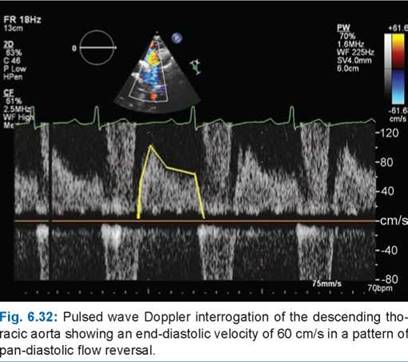

In significant aortic regurgitation, we know a substantial amount of blood regurgitates back into LV. This backflow though happens in the chest and into the LV, it is reflected all over the vascular tree. It so happens, the entire aortic forward flow for a moment slows in end-systole or even reverses at the end-systole and early diastole when the Aortic valve leaks. Almost all peripheral signs of AR are due to this. It is critical to remember, that these signs are heavily modified by arterial distensibility, associates obstruction, LV contractility, and peripheral vascular resistance.

Now, we are able to document bizarre hemodynamics that happens the entire length of the vascular tree that is responsible for this murmur.(A related post 😦 In AR the run-off is central or periphery ?_)

Phoncardiography with ECG correlation, help us to time the murmur exactly and also demonstrates reversal of flow in femoral artery by color flow doppler.

Though it’s of historical interest, it is still discussed in exams. It may be amusing for the busy clinical cardiologist to auscultate over the legs, when they may be contemplating a TAVI for leaky Aortic valve (Arias EA, Interv Cardiol. 2019). But, for students, it is a different story. If anyone wants to beat the acumen and curiosity of Duroziez, they may assess the length of this murmur and correlate it with descending aortic flow reversal, aortic ERO, and regurgitant fraction. The fate of Duroziez’s murmur after Aortic valve replacement may also be studied.